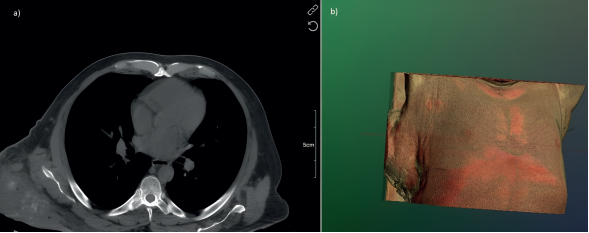

En el examen físico, el paciente se encontraba consciente, orientado y cooperativo. Se identificó un tumor de 20 × 15 cm en la región dorsal, a nivel infraescapular derecho. La masa era de consistencia blanda, con signos de hiperemia, dolor a la palpación y secreción purulenta de olor fétido. Se decidió iniciar el protocolo diagnóstico con una tomografía computarizada (figura 1).

Imágenes: Calderón Valderrama, et al.

Figura 1 a) Tomografía axial de tórax en fase simple, ventana para mediastino, que muestra una gran lesión en tejidos blandos, isodensa al plano muscular. Se identifican imágenes nodulares hipodensas sugerentes de necrosis, así como imágenes lineales hiperdensas compatibles con calcificaciones. b) Reconstrucción volumétrica que evidencia el tamaño significativo de la lesión.